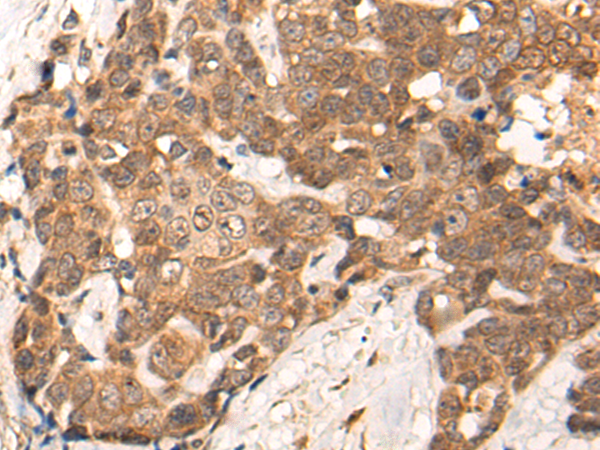

IHC positive control:

Human liver cancer and human breast cancer